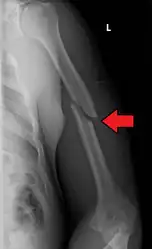

A transverse fracture of the humerus shaft -

A spiral fracture of the distal one-third of the humerus shaft -